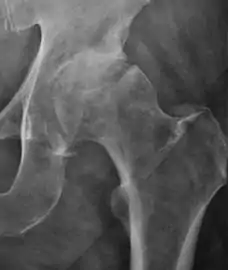

- Osteoarthritis

In adults, one of the main indications for radiographs is the detection of osteoarthritic changes (Figure 1(e)). Nevertheless, radiographs usually detect advanced osteoarthritis that can be graded according to the Tönnis classifications. The grading system ranges from 0 to 3, where 0 shows no sign of osteoarthritis. Intermediate grade 1 shows mild sclerosis of the head and acetabulum, slight joint space narrowing, and marginal osteophyte lipping. Grade 2 presents with small cysts in the femoral head or acetabulum, moderate joint space narrowing, and moderate loss of sphericity of the femoral head. Grade 3 is the severest form of osteoarthritis, which manifests as severe narrowing of the joint space, large subchondral cyst with productive bone changes that may lead to deformity of the bone components of the joint, while secondary osteoarthritis due to calcium pyrophosphate deposition can be diagnosed when calcification of hyaline cartilage and fibrocartilage is detected.[1]

There are other pathological conditions that can affect the hip joint and radiographs help to make the appropriate diagnosis. Acute bacterial septic arthritis can be diagnosed by radiographs when a fast regional osteoporosis and destructive monoarticular process develops (Figure 1(f)). In case of tuberculous or brucella arthritis it is manifested as a slow progressive process, and diagnosis may be delayed.[1]